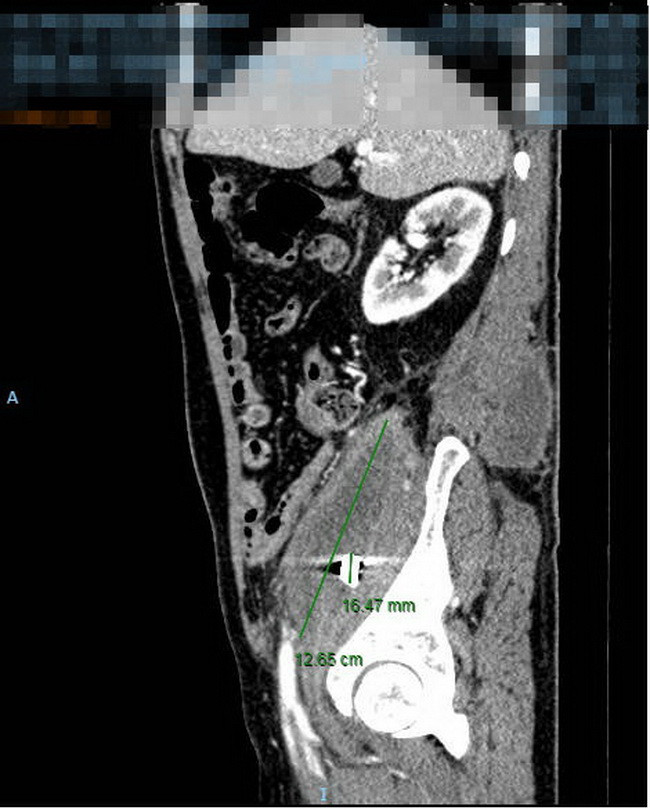

| Viên đạn được lấy ra từ người bệnh. |

Sau khi rạch phá rộng ổ áp xe, ca mổ đã lấy ra hơn 500ml mủ đặc. Với mong muốn tha thiết được các bác sĩ lấy mảnh đạn ra khỏi cơ thể để không còn bị hành hạ bởi các cơn đau của người bệnh, cùng quyết tâm cứu chữa cho người bệnh của êkip các bác sĩ phẫu thuật và sự hỗ trợ của các trang thiết bị đầy đủ, mảnh đạn đã được lấy ra khỏi ổ bụng của người bệnh với kích thước 1x1cm, nhiều cạnh sắc”.